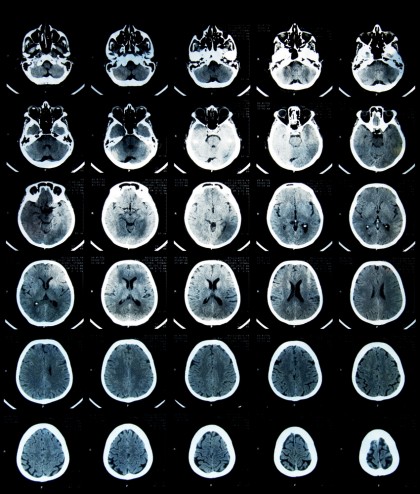

Bolnavii de cancer pulmonar cu metastaze la creier ar putea fi scutiți de radioterapie craniană

În Marea Britanie, în jur de 45.500 de persoane sunt diagnosticate anual cu cancer pulmonar, aproximativ 85% dintre aceste persoane suferind de cancer pulmonar fără celule mici. Până la 30% dintre aceștia din urmă ajung să aibă metastaze la creier. Radioterapia craniană implică vizite zilnice la spital și efecte secundare ca pierderea părului, dureri de cap, oboseală, stări de greață, neîndemânare, scalp uscat sau cu prurit și dificultăți de concentrare. Acestea sunt motivele pentru care cercetătorii au dorit să stabilească dacă radioterapia craniană îmbunătățește cu adevărat durata de supraviețuire și calitatea vieții la acești pacienți.